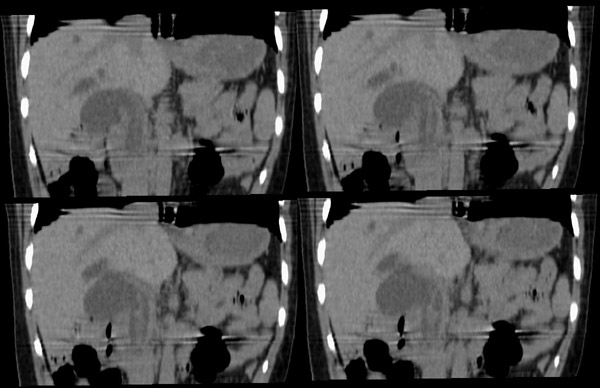

胆总管矢状及冠状重建:

整个胆道系统内可见多发蛔虫钙化改变,胆道扩张.

胆总管结石并肝内外胆管扩张、肝左叶肝内胆管结石、胆囊大。

行胆囊切除术及胆总管探查术:探查见肝脏大小正常,肝缘稍钝,肝表面光整,胆囊大小12*3*3cm3,壁水肿增厚约0。5cm,张力稍高,胆囊与大网膜呈纤维粘连;胆总管宽约2cm,壁明显增厚,触摸胆总管,隐约可触及一条状物,于胆总管做一长约1、5cm的纵行切口,用取石钳在胆总管内取出一条长约16cm长黑色的长条状物,较脆易折断,宽约0、6cm,证实为蛔虫尸体。用探子往下探,未发现下端结石最后诊断:胆道蛔虫症继发胆系梗阻性扩张。